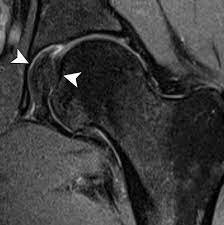

Hip Labral Tear